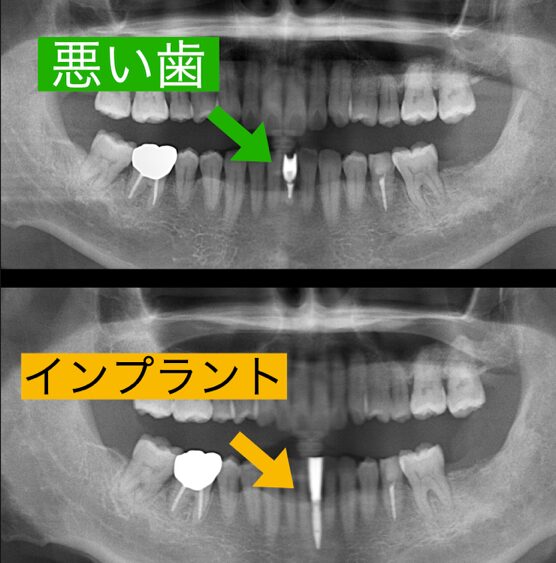

患者様は左下中切歯の歯折と根の付近から膿が止まらないというお悩みで来られました。CT撮影を行うと根先病巣は大きく、根の先は炎症で吸収されており根管治療では保存ができない状態でした。 そのことを患者様にお伝えしたところ、悪い歯を抜いてインプラント治療を行いたいとのことでした。数年前までならこの狭いスペースに埋入できるインプラントは存在せず、ブリッジが主流でしたが、最近2.8ミリという極細のインプラントが新製品として発売されました。それを使用することによって両隣りの歯を削る必要がなくなります。患者様はそれを強く望まれたので細いインプラントで治療をすることになりました。

抜いてその日にインプラントを入れる抜歯即時インプラントの術式を選択しました。シミュレーションを行いデンサーバーという特殊なバーで骨質改善を行い、骨を硬くしてインプラントを埋入することになりました。

インプラント手術は抜いたその日に入る抜歯即時埋入で行いました。抜歯はすぐに終わったのですが、膿がかなりあり掻爬に時間がかかりましたが、ここをおろそかにするわけにはいきません。しっかりと膿取りを行い、デンザーバーで形成し細い2.8ミリのインプラントを埋入しました。